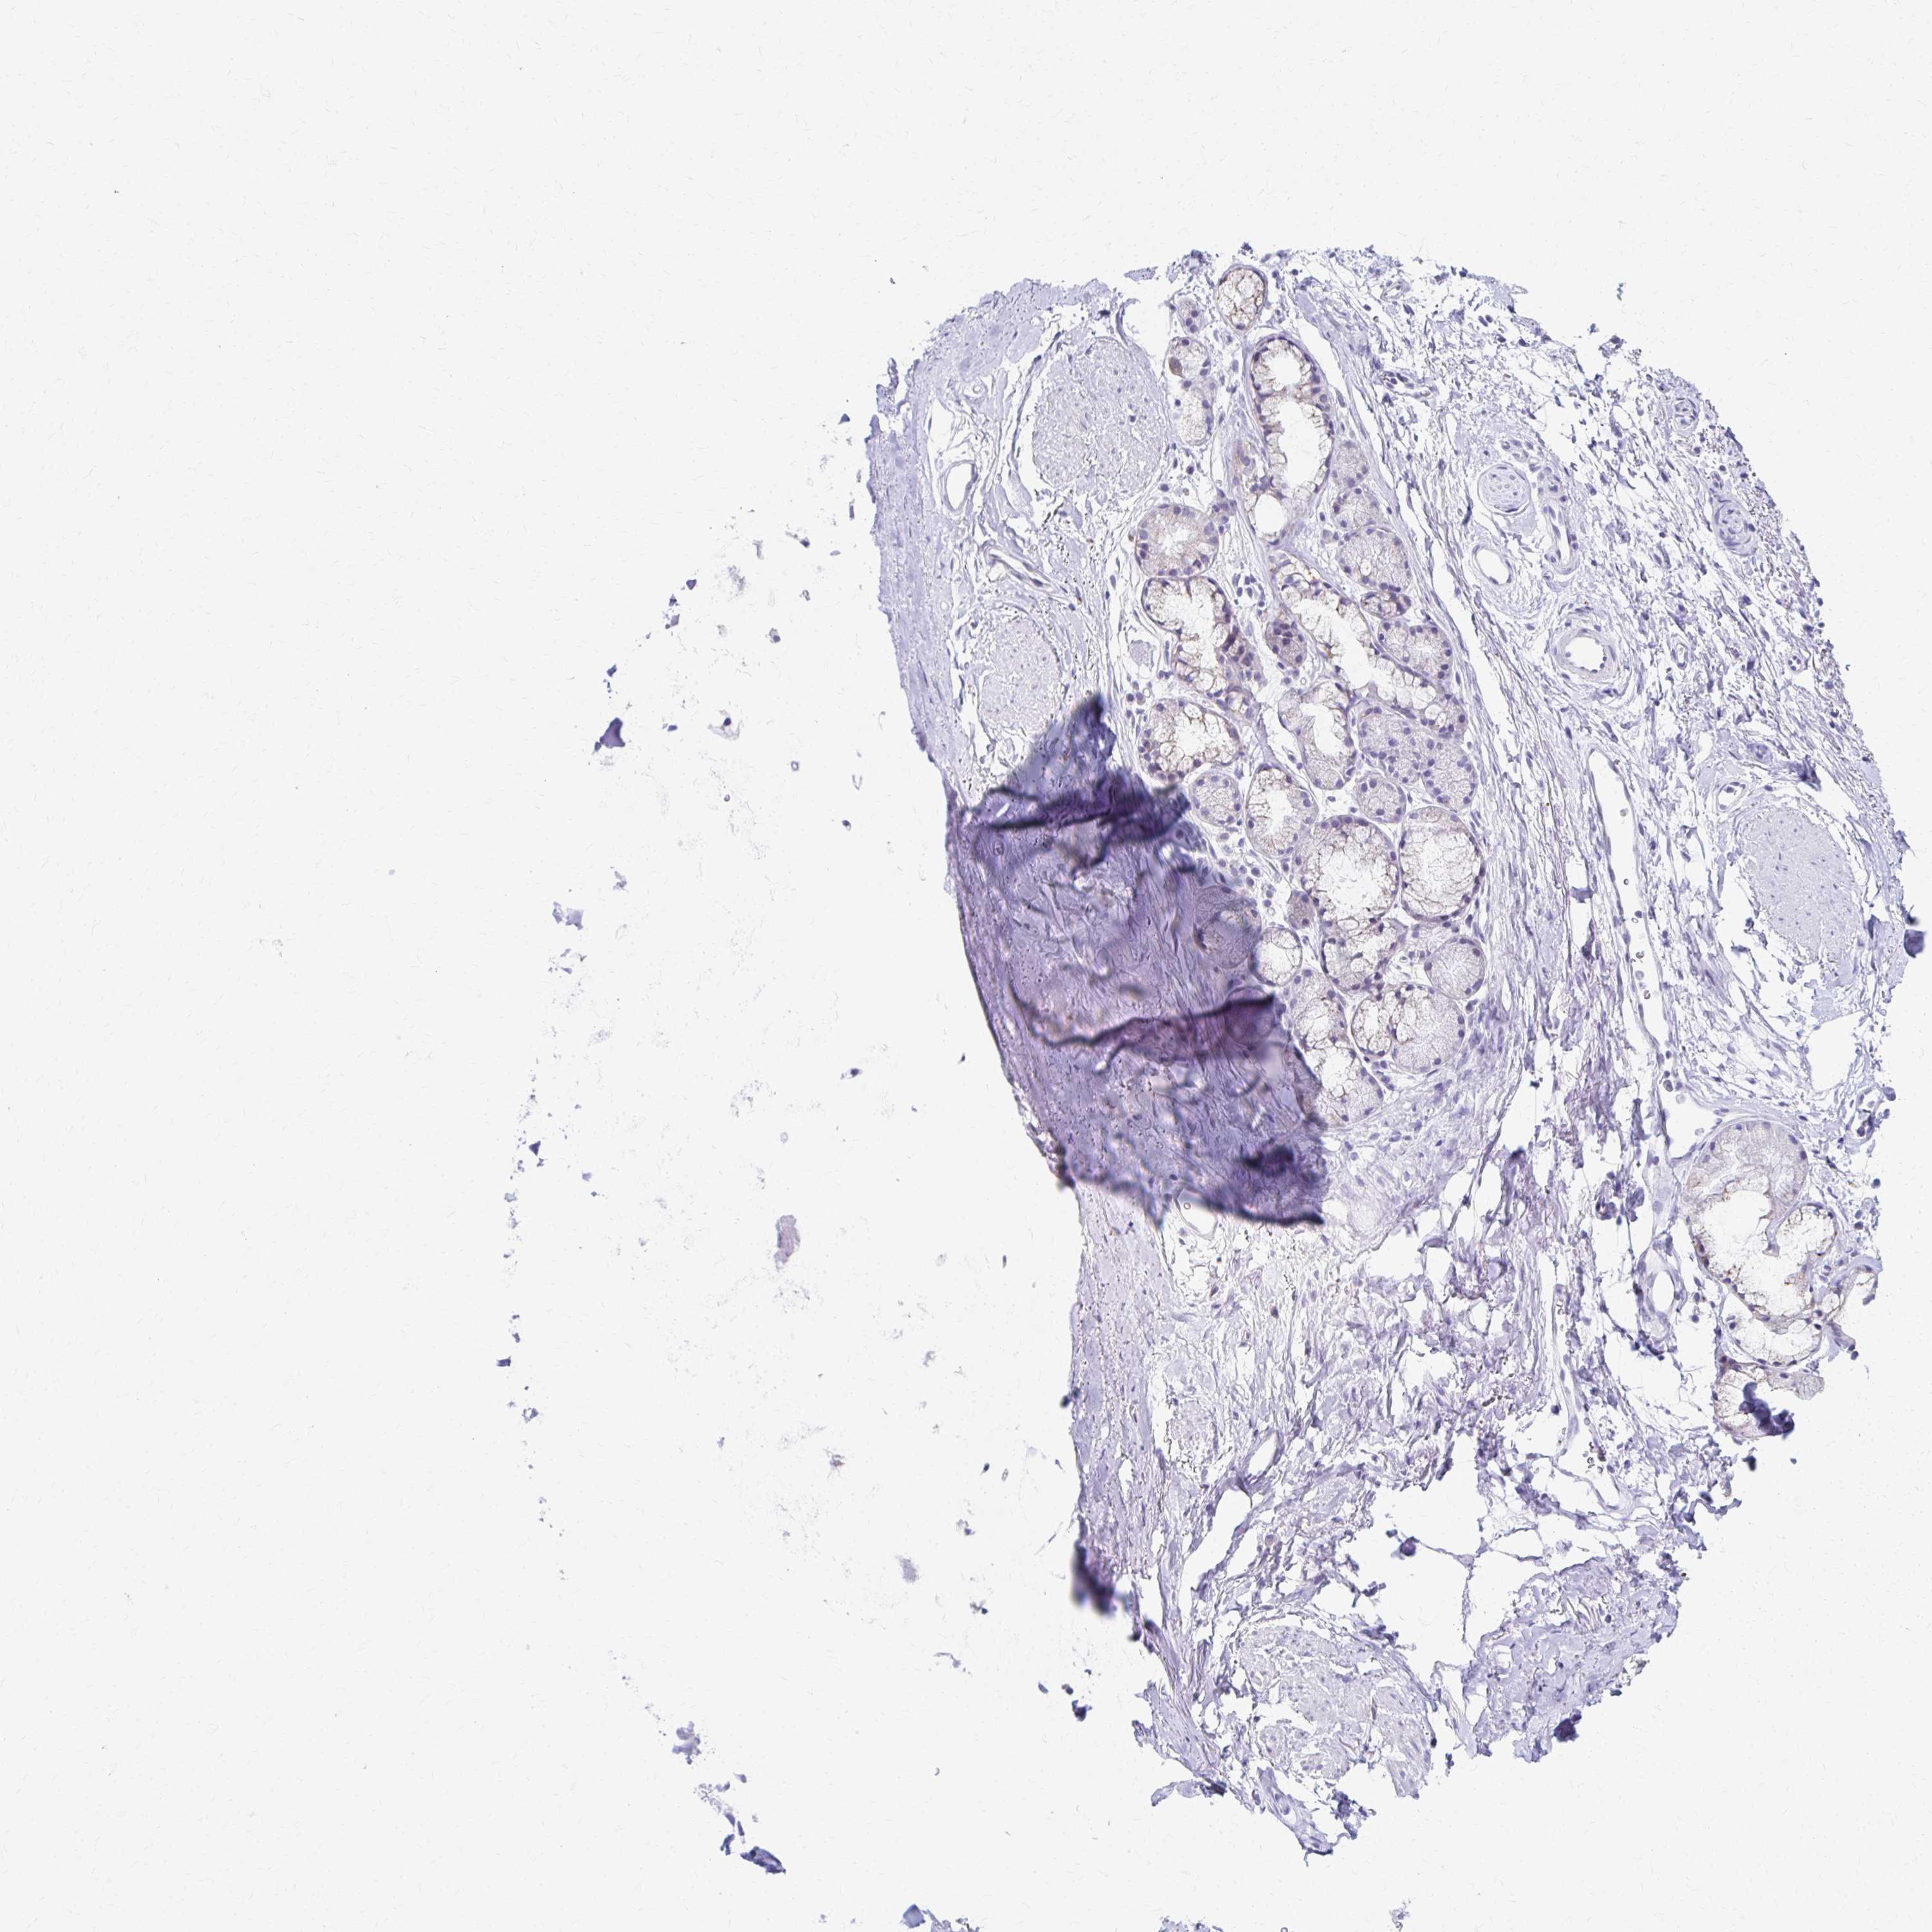

PRKCG